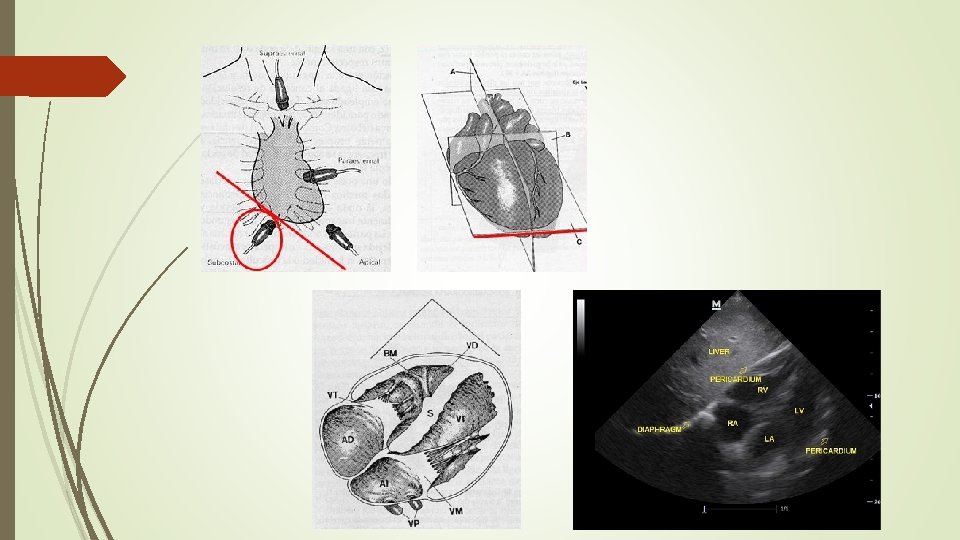

4. - SUBCOSTAL Visualizar el corazón desde el hipocondrio derecho/epigastrio utilizando el hígado como ventana acústica. Plano TRANSVERSAL, hipocondrio derecho/Epigastrio, angulación cefálica del transductor. DERECHA IZQUIERDA

EVALUAR Visualización 4 cámaras. Valorar líquido pericárdico (Derrame pericárdico)